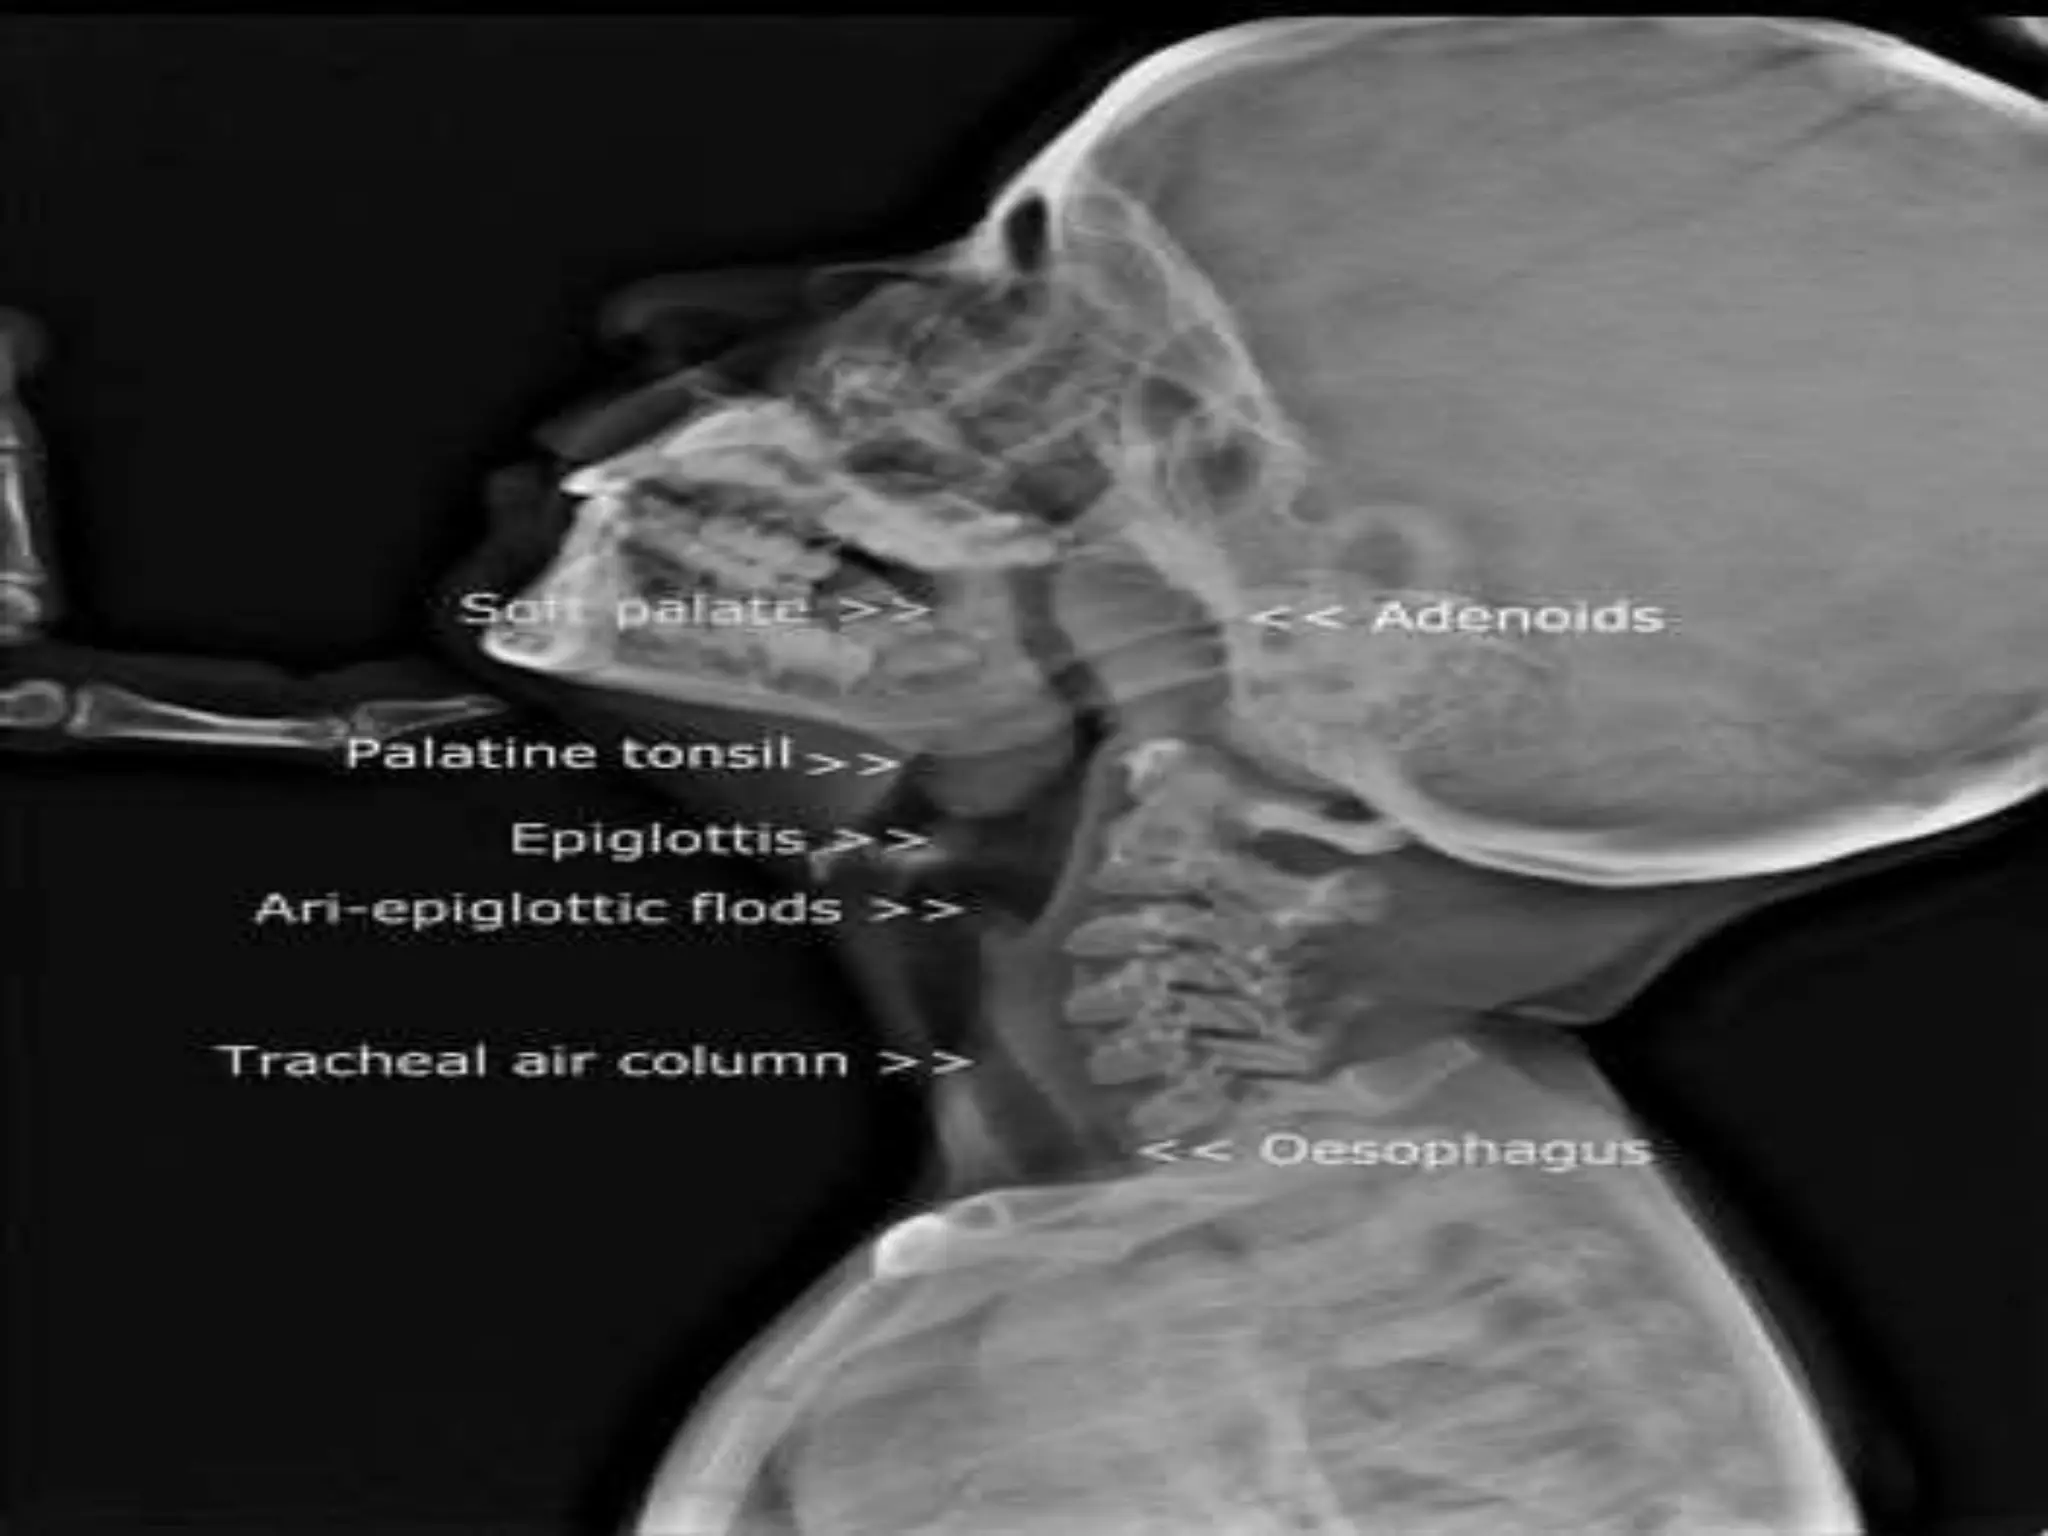

What are adenoids? Adenoid Hypertrophy, Clinical features and